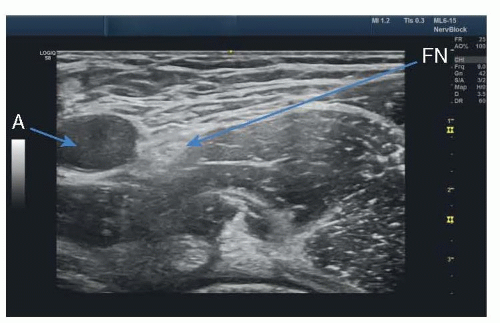

The adductor canal block is often performed in a location that is proximal to the true adductor canal, near the point at which the sartorius muscle covers the femoral vessels. The nerve can be visualized next to the femoral artery, just deep to the sartorius muscle (FIG 2).

FIG 2 • Ultrasound image of adductor canal block. SN, saphenous nerve; SM, sartorius muscle; A, femoral artery; V, femoral vein.